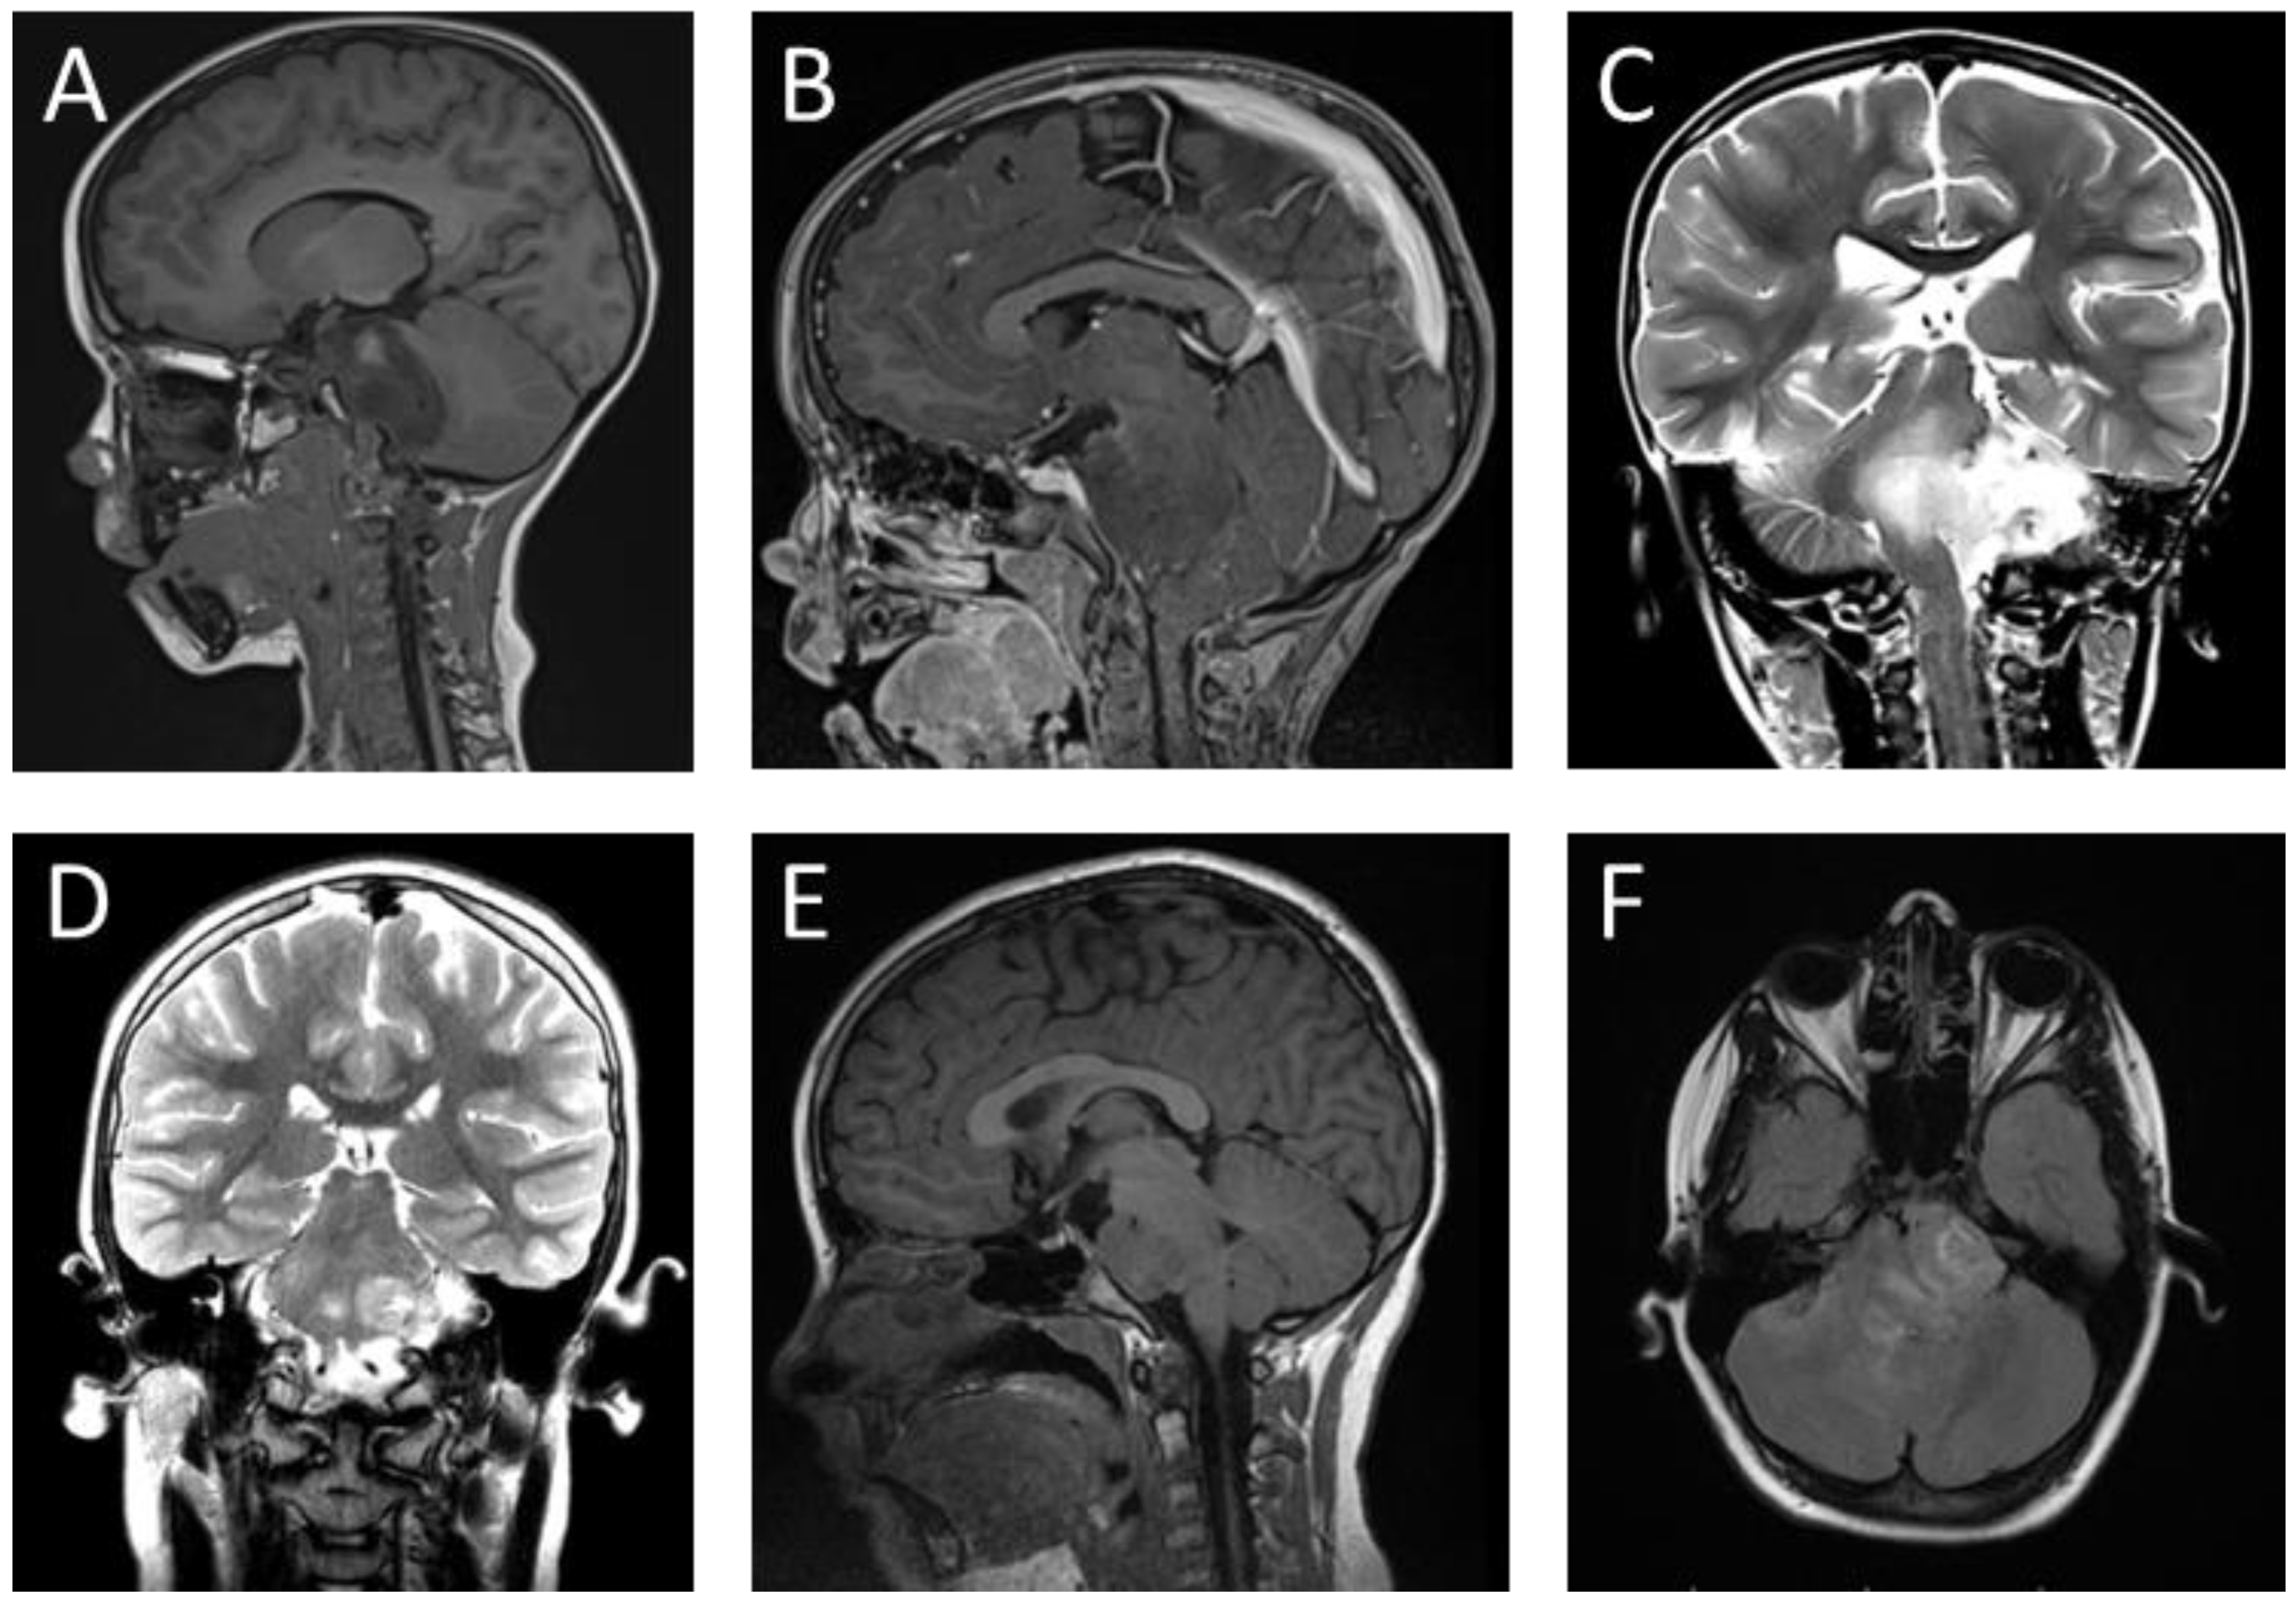

Figure 3. Representative histology of pediatric DMG. Histologic geographic variability of DMG. ×4 (A,C) and ×20 (B,D). Hematoxylin and eosin stains from different sections of a single tumor showing low-grade (A,B) and high-grade (C,D) areas. (E) Immunohistochemical staining of the same sample using antibody directed to the H3K27M epitope. The sample is strongly positive. (F) Immunohistochemical staining of mutant p53, a common co-occurring mutation in DMG. (AD) Reprinted with permission and adapted from Warren et al. (2012) [15] and (E,F) reprinted with permission and adapted from Srikanthan et al. (2021) [35].